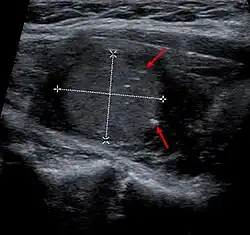

Imagen de un cáncer medular de tiroides en una ecografía. Las flechas marcan las calcificaciones.

Esta forma de cáncer se origina en las células parafoliculares (células C), las cuales producen calcitonina y comprenden entre el 3-6% de todos los cánceres tiroideos. La calcitonina es una hormona que puede producir hipocalcemia. La calcitonina es un marcador útil para detectar este tipo de cáncer y monitorizar la respuesta a los tratamientos. El antígeno carcinoembriogénico (CEA) también es útil como marcador tumoral en esta situación. Hasta el 25% de estos tumores pueden ser familiares.[5]​ Por ello en estos casos se recomienda el estudio de mutaciones germinales del gen RET.[5]​ En concreto, se deben evaluar mutaciones en los exones 10, 11, 13-16,[3]​ y si son negativas se piden también las mutaciones del exón 8. Aproximadamente 6 a 8% de los pacientes con cáncer medular de tiroides aparentemente esporádico tienen mutaciones del proto-oncogén RET en la línea germinal. No obstante, los estudios han encontrado mutaciones entre el 1.5% y el 25%. Por el contrario, las mutaciones somáticas (sólo presentes en el tumor, pero no en el ADN leucocitario) están presentes en el 50% de los casos. El tratamiento de los portadores asintomáticos de mutaciones en la línea germinal (familiares del paciente) tiene un gran impacto pronóstico, con tasas de curación del 95%. La penetrancia de la mutación es del 100%. El pronóstico de este tipo de tumor es malo cuando se presenta en fase avanzada. Puede producir metástasis en diversos órganos como hígado, hueso, pulmón y ganglios linfáticos.